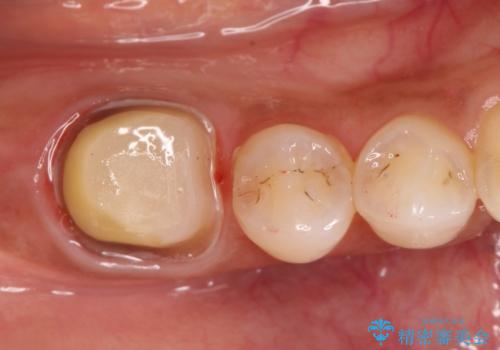

- 奥歯が痛いことを主訴に来院されました。

根管治療を行なったのちオールセラミッククラウンにて修復補綴を行いました。

根管治療歯は破折を防止するために速やかに被せ物の治療を提案いたします。